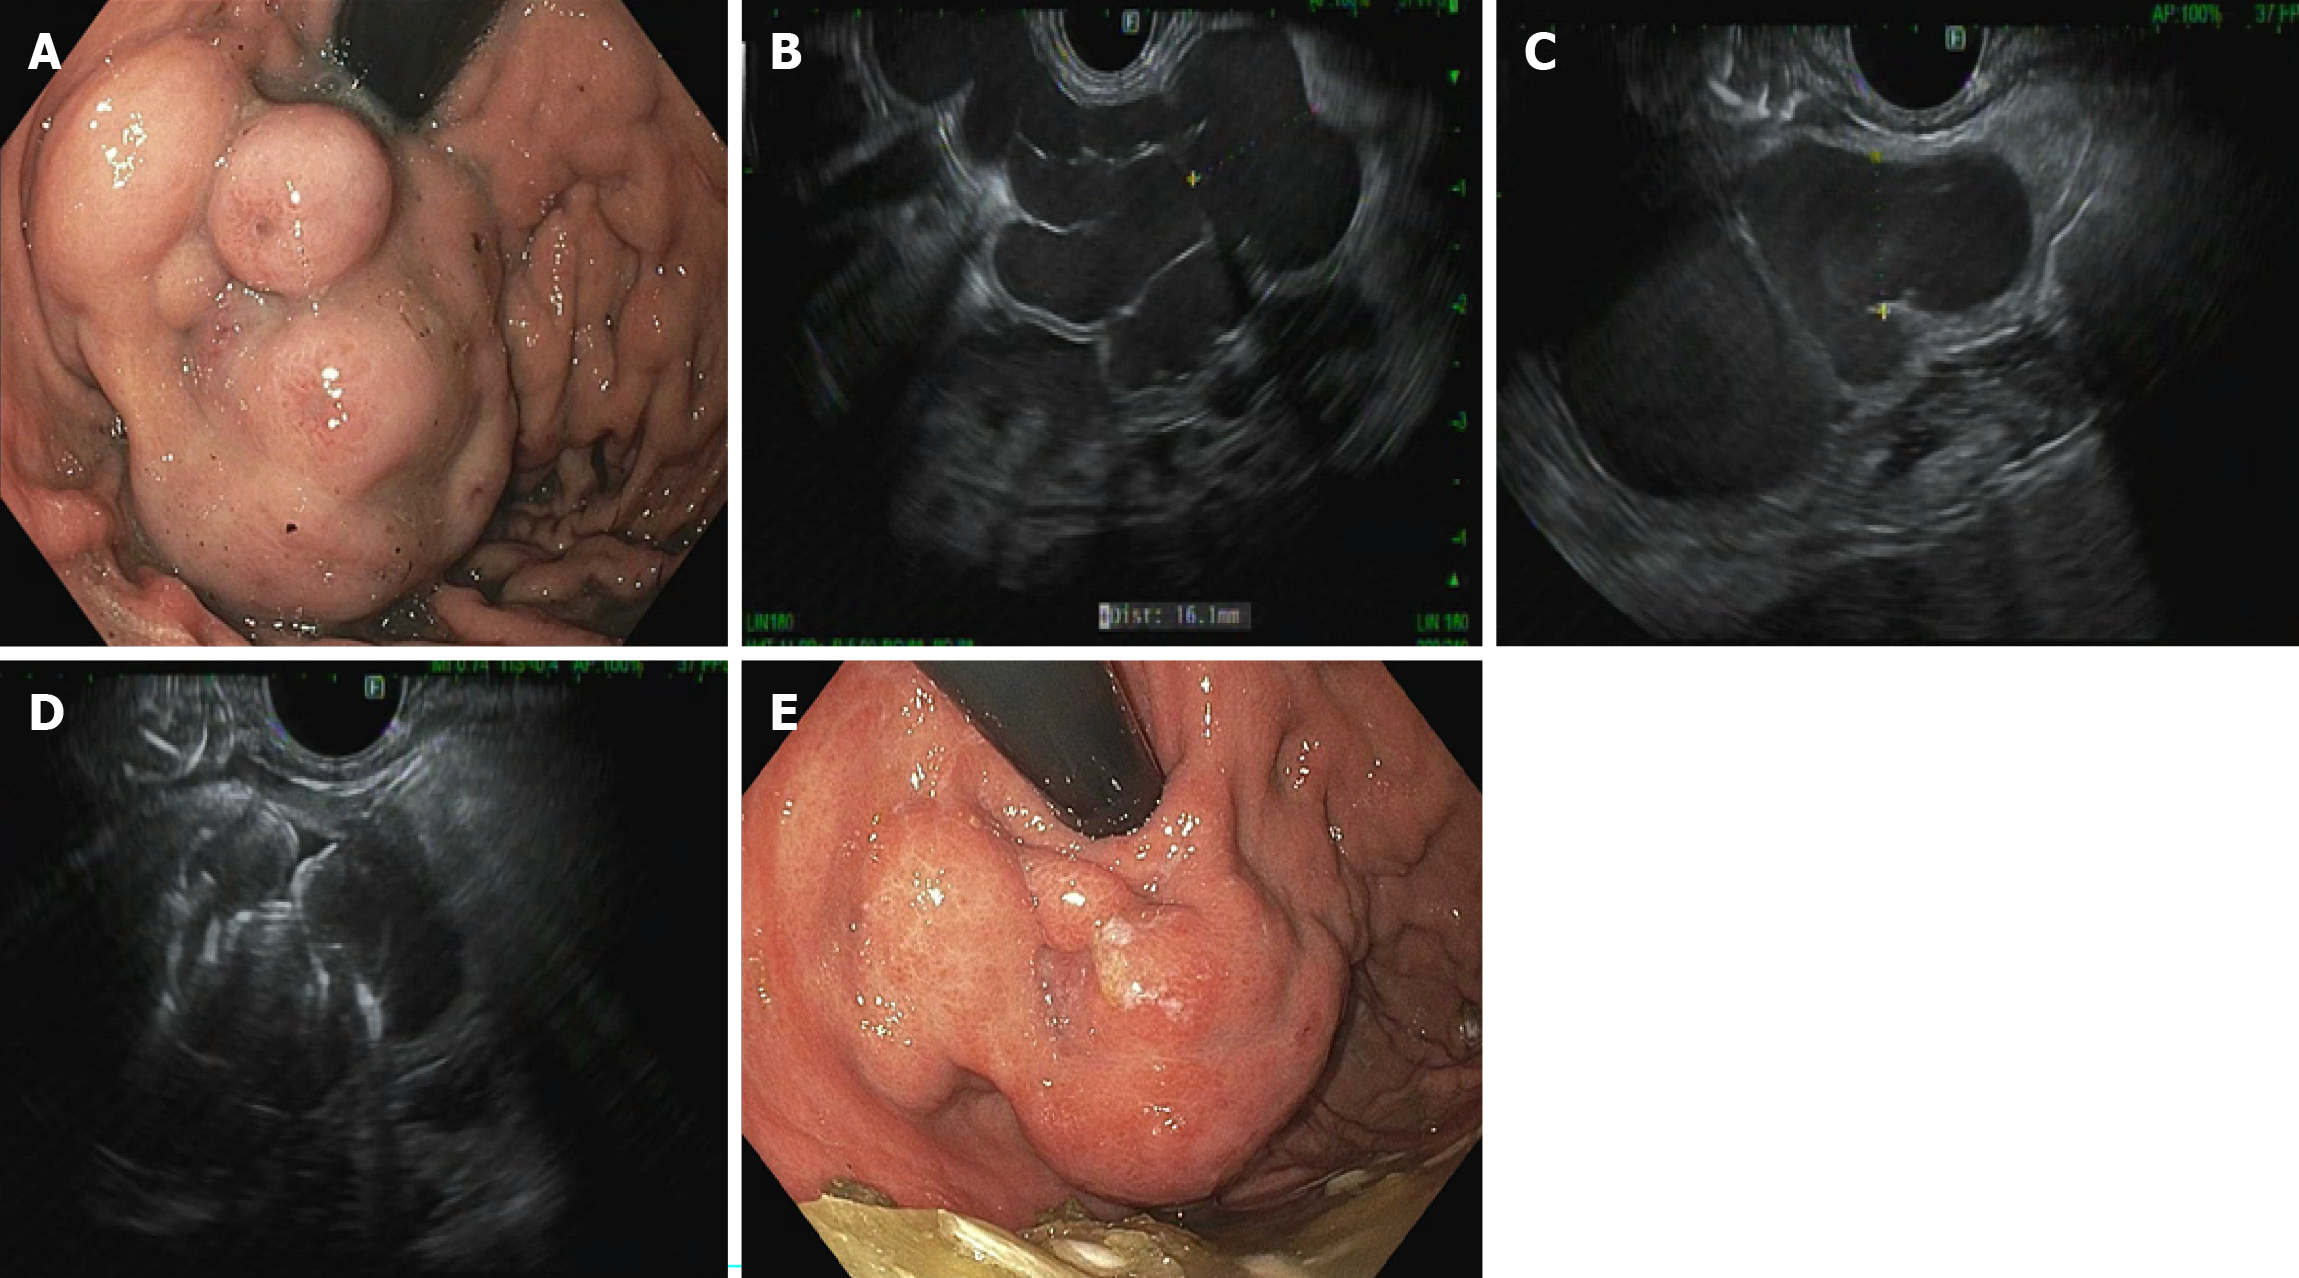

Figure 2

Figure 2 65-year-old female with history of metabolic dysfunction associated steatohepatitis cirrhosis presented with hematemesis and melena. A: Upper endoscopy showed large gastroesophageal varices type 2 with stigmata of recent bleeding; B: Endoscopic ultrasound (EUS) showing a large variceal conglomerate; C: The feeder vessel was located under EUS evaluation; D: Transesophageal deployment of multiple coils and absorbable gelatin sponge (Gelfoam slurry) under EUS guidance; E: Improvement in size of varices following EUS-guided coil embolization.